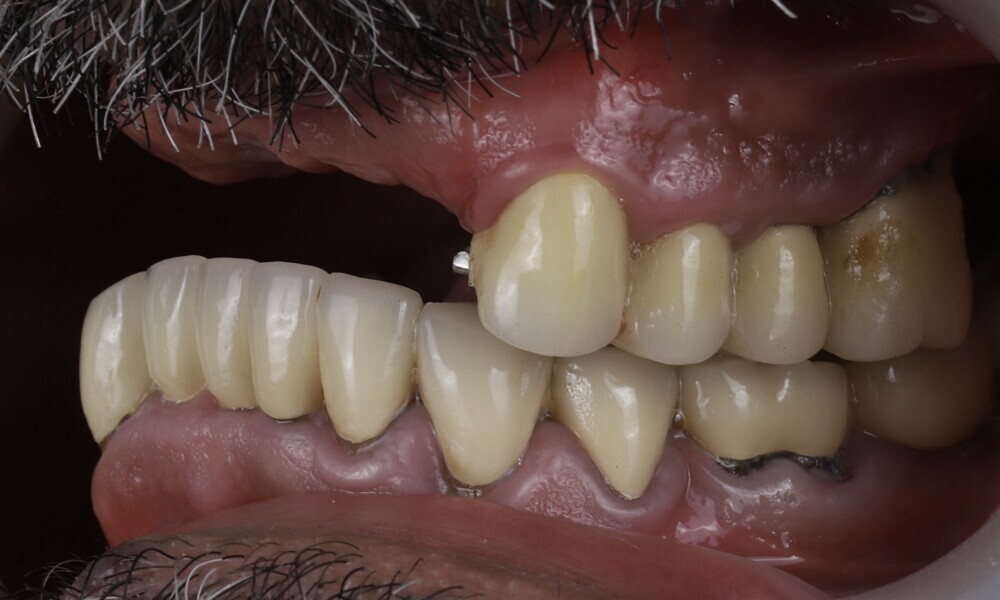

Employing a fully guided surgical protocol alongside a completely digital prosthetic workflow allowed for the precise design and milling of a PMMA provisional prosthesis (Figs. 34 & 35). The implant loading protocol implemented was immediate loading with equal distribution of forces across the entire prosthesis. The patient received the screw-retained provisional prosthesis on the same day. Temporary abutments (titanium copings) were placed on top of the screw-retained abutments. The spaces between the titanium copings and the provisional prosthesis were filled (Figs. 36–38). Any excess material was cut away, and the provisional prosthesis was subsequently polished to ensure a smooth finish (Fig. 39). The provisional prosthesis was then attached and securely fixed to the titanium copings to a 15 N cm torque (Fig. 40). Oral hygiene instructions were provided, and the occlusion was assessed (Figs. 41 & 42). A final control radiograph was obtained and confirmed that all parameters were within normal limits (Fig. 43).

During follow-up visits, the patient exhibited excellent healing and no postoperative complications (Fig. 44). The provisional prosthesis demonstrated optimal fit and stability, enhancing function and the patient’s comfort.

Four months later, we proceeded with the final prosthetic procedure based on clinical and radiographic evidence confirming osseointegration. The case was completed using Straumann RevEX scan bodies for a full monolithic design with a completely digital workflow. First, an intra-oral scan of the opposite arch was taken, followed by an intra-oral scan with the screwed-in temporary abutments. An intra-oral bite scan and an intra-oral scan of the soft tissue with the screw-retained abutments in place were then taken. The reverse scan bodies were attached to the provisional prosthesis, which was scanned extra-orally. Next, the prototype and verification jig were designed, followed by the milling of the prototype and verification jig (Figs. 45 & 46).

During the next visit, the milled prototype and verification jig were tried in, and the design and manufacturing of the final prosthesis were completed (Figs. 47 & 48). The final abutment utilised was Variobase for bridge (Straumann), placed on top of the screw-retained abutments. The material chosen for the final prosthesis was monolithic zirconia (Figs. 49 & 50).

The delivery of the final prosthesis was then performed, and the aesthetics, occlusion and function were verified (Figs. 51–55). The panoramic control radiograph showed that all measurements were within expected ranges (Fig. 56).